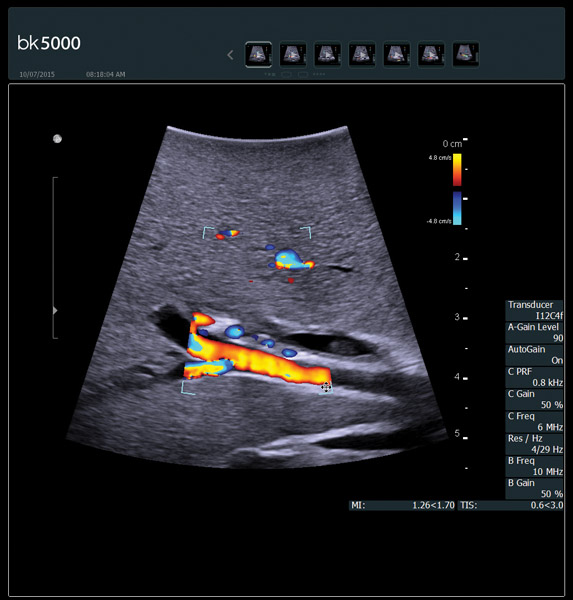

Addressing Challenges with Advanced Technologies

From the simplest diagnostic imaging to the most critical interventional procedures, every clinical situation has its own set of unique challenges. The bk5000 offers a full suite of innovative technologies and advanced controls and adjustments to help you achieve the best possible image quality, across many applications.